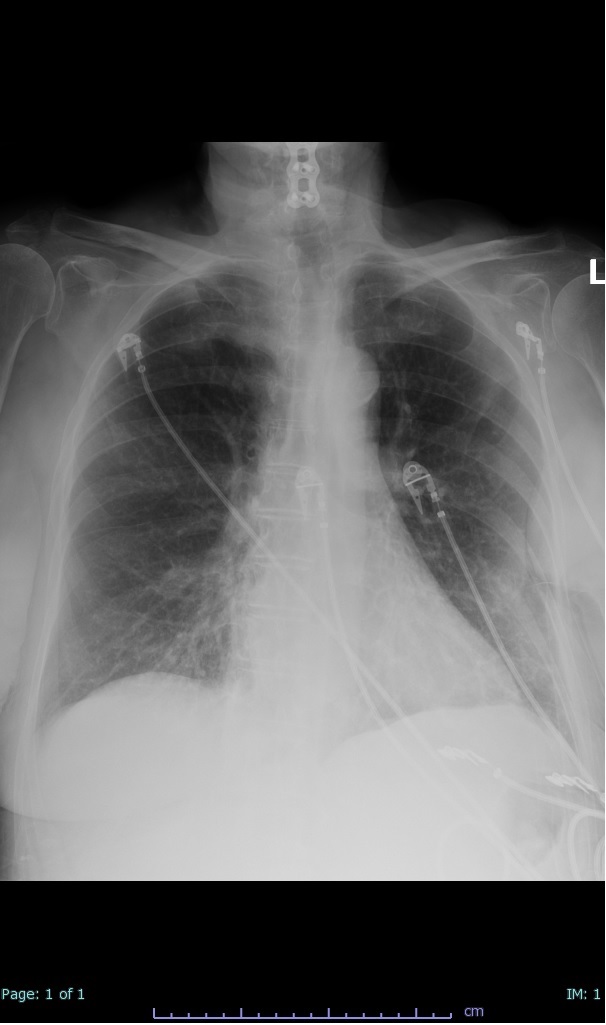

- 66% had some + CXR finding I could correlate to a CT finding

- 66% had documented exposure, rest I couldn't find either way

I'll list age decade and + exposure documented #covid19 #coronavirus #radiology #FOAMed #radres 2/17